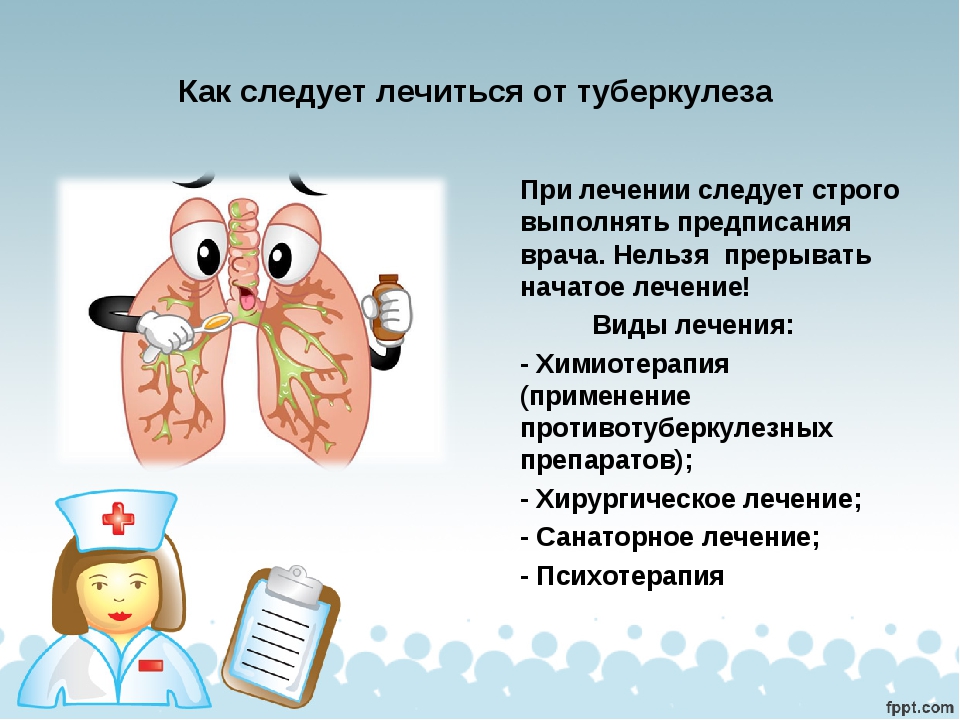

Симптомы туберкулеза: Как распознать и что делать

Раздел: Визуальные уроки